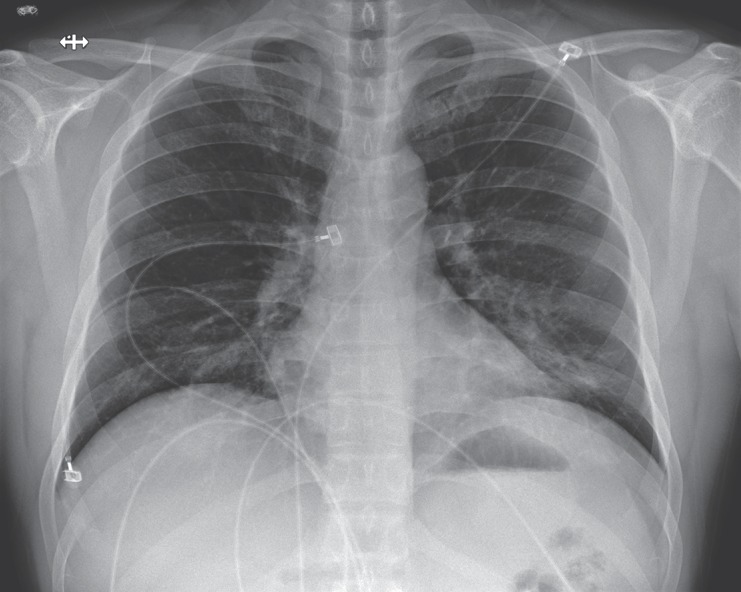

Description:An outbreak of novel coronavirus (2019-nCoV) that began in Wuhan, China, has spread rapidly, with cases now confirmed in multiple countries. We report the first case of 2019-nCoV infection confirmed in the United States and describe the identification, diagnosis, clinical course, and management of the case, including the patient's initial mild symptoms at presentation with progression to pneumonia on day 9 of illness. This case highlights the importance of close coordination between clinicians and public health authorities at the local, state, and federal levels, as well as the need for rapid dissemination of clinical information related to the care of patients with this emerging infection.